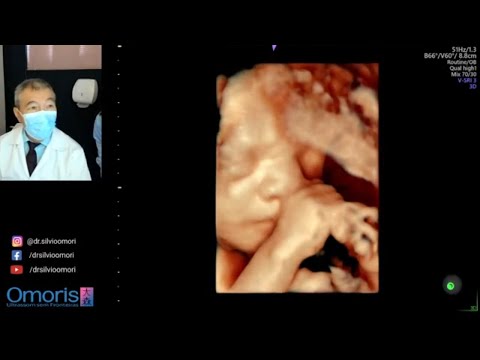

УЗИ плода: Гипоплазия Мозжечка. Вентрикуломегалия. Кость Носа. Единственная артерия пуповины.

02:24 Гипоплазия мозжечка. Несоответствие неделе беременности. 07:01 Вентрикуломегалия (расширение желудочков мозга) на УЗИ при беременности. 11:50 Билатеральная верхняя полая вена. 13:45 Единственная артерия пуповины. 14:55 Гипоплазия костей носа. Привет. Я - Оля, живу и практикую в Мюнхене. На моём канале - о беременности, родах, периоде новорожденности с точки зрения современной медицины. Инста: @we2plus3 Почта: akusherka@yahoo.com